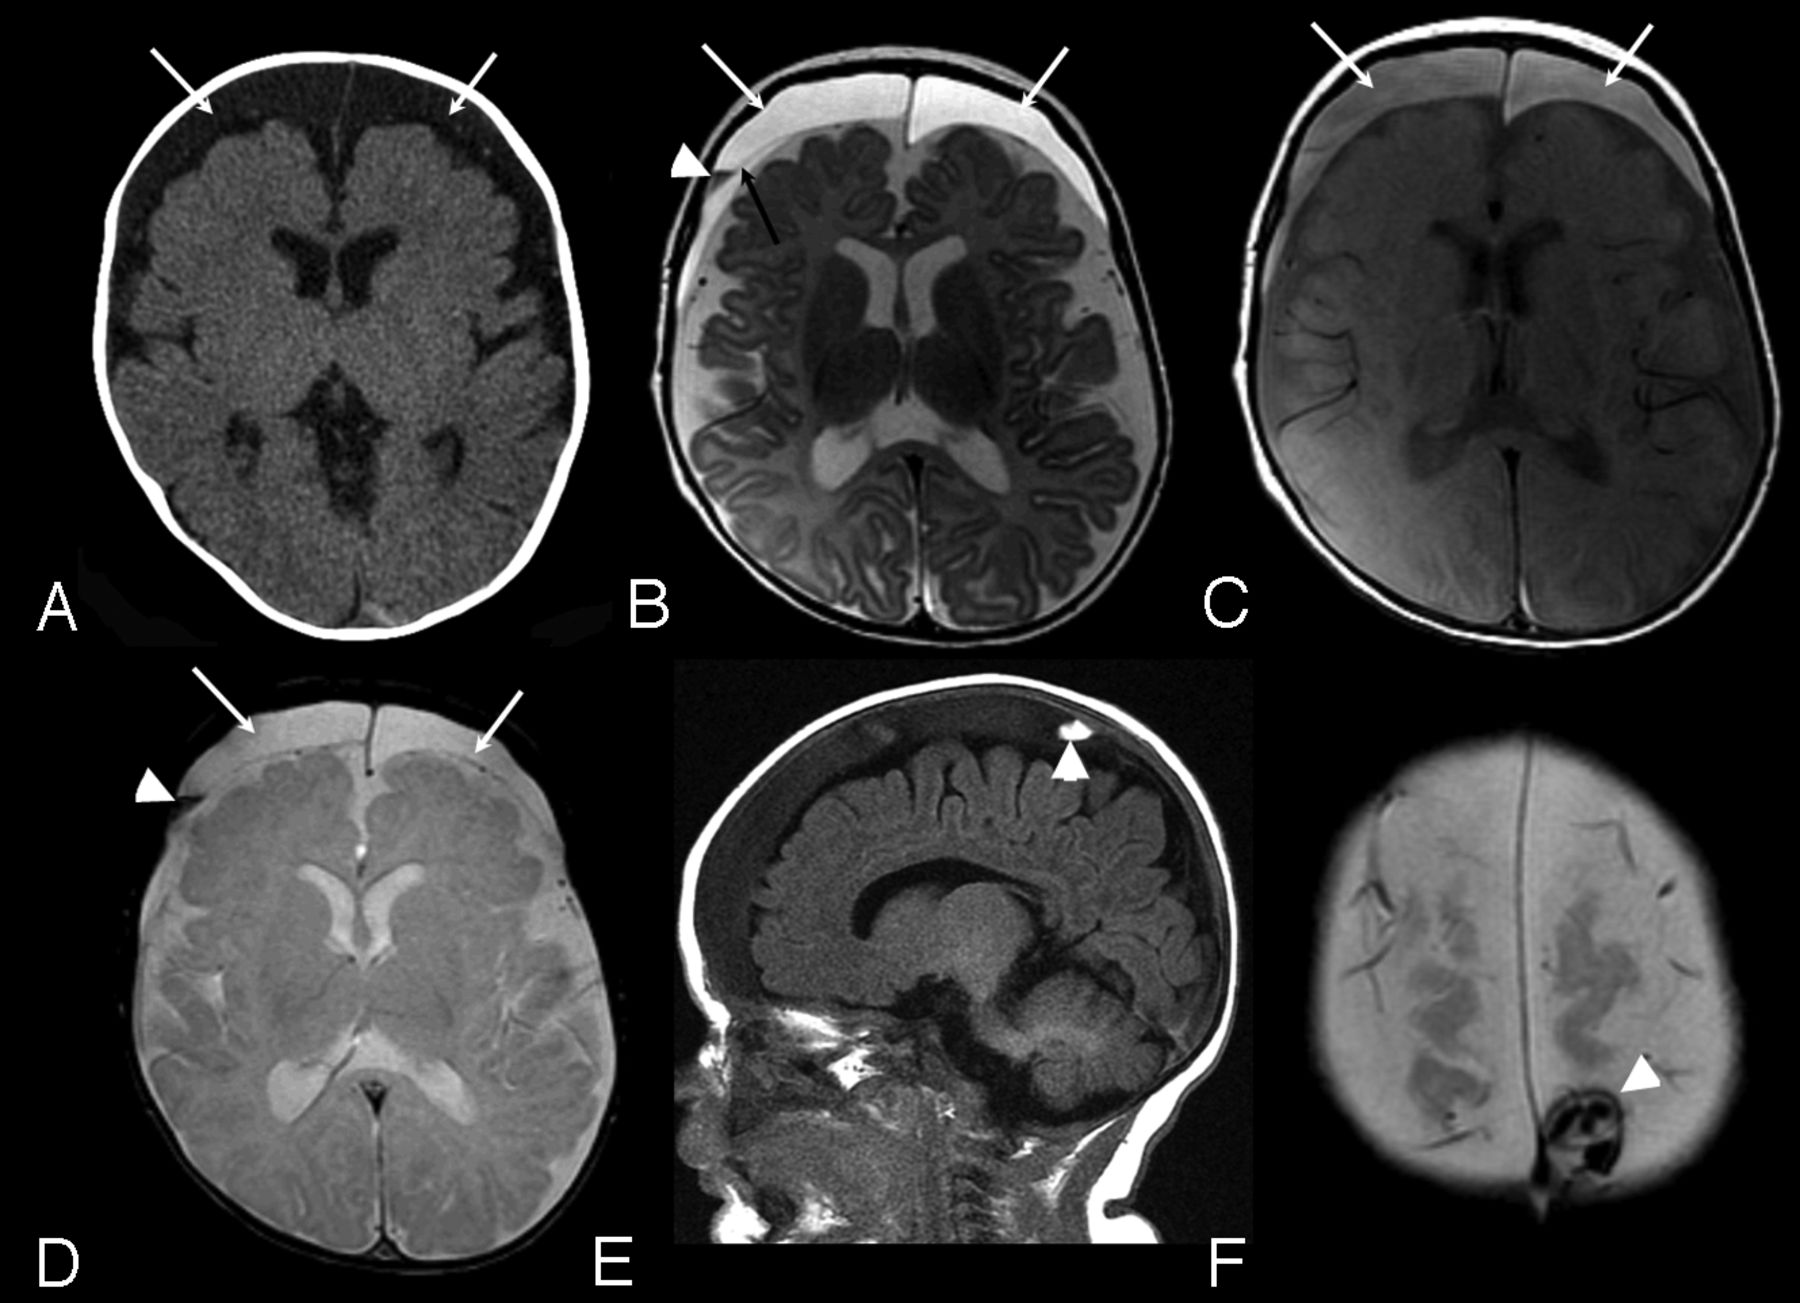

The SDC were identified initially on CT in 2 cases and on MRI in 4 (On-line Table). All SDC cases were referred because of macrocrania. Both CT cases had MRI within 9 days, which confirmed the CT findings. SDC were bilateral in 2 cases and unilateral in 4, localized over the convexities, with a mean size of 5.4 mm (range, 1–9.6 mm). In 4 cases (cases 2, 3, 5, and 6), the SDC were homogeneous, unilateral, and small in size, with similar features on MRI (Fig 1). None of these subjects had recent (within 2 weeks) CT imaging for review. In 2 cases, the SDC were larger, bilateral, and complex in appearance. In case 4, there were heterogeneous signal changes on MRI and increased attenuation on CT, which suggests recent hemorrhage with identified membranes within the collections (Fig 2). In case 1, there was heterogeneous internal signal with visible membranes and different signal intensity components. No CT or gradient-echo evidence of acute hemorrhage was identified.

Case 4. A, Axial CT image. B, Axial FSE T2-weighted image. C, Axial proton density–weighted image. D, Axial gradient recalled-echo image. E, Sagittal T1-weighted image. F, Axial gradient-echo image: 3-month-old boy with macrocrania. Initial CT examination (A) demonstrates moderate sized bilateral subdural collections (arrows), slightly hyperattenuated relative to CSF. MRI examination was performed 14 hours later. Bilateral subdural collections are again identified (white arrows, B, C, and D) hyperintense to CSF on both T2 and proton density–weighted images (B and C). A thin septation is identified on the right (black arrow, B). A layering region of decreased T2 signal is seen on the right (arrowhead, B), which was hyperintense to CSF on T1-weighting (not shown) and blooms on the gradient-echo sequence (arrowhead, D) compatible with blood products. A localized area of increased signal on T1-weighted images in the right parietal vertex subdural collection was noted (arrowhead, E), which was hyperattenuated to brain on CT (not shown) and exhibited blooming on the gradient-echo sequence (arrowhead, F) consistent with additional blood products.

A multidisciplinary CAT consultation was requested for 2 of 6 cases with SDC (cases 1 and 4). Both had normal initial and follow-up skeletal surveys, and both had dedicated retinal examinations. In case 1, there were retinal hemorrhages characteristic for abuse. Two additional children with SDC had dedicated retinal examinations for hyperopia and astigmatism, and no retinal hemorrhages were seen. None had unexplained bruising. One child (case 6) with small, homogeneous, unilateral right-sided SDC had a history of a left-sided parietal skull fracture 3 months before the index examination. A CAT consultation at that time resulted in clinical findings consistent with accidental trauma. On CT examination at the time of skull fracture, the SS were noted to be prominent; however, no intracranial hemorrhage or SDC were identified. Ultimately, 2 children were reported to Children's Services as probable abuse, including the case with the retinal hemorrhages and complex SDC (case 1) and the case with the signal changes suggesting recent hemorrhage (case 4). The remaining 4 cases not reviewed by the CAT were not reported to Children's Services.

Although numbers are small and the clinical child abuse directed assessment was not performed on all patients, our report suggests small homogeneous SDC on cross-sectional imaging, without definite evidence of hemorrhage, may occur in the setting of BESS and may not indicate inflicted injury. In our study, 2 of the 6 children with SDC had findings suggesting child abuse. Both of these subjects had moderate-sized, bilateral, heterogeneous collections. The remaining 4 patients had radiographically similar SDC that were small, homogeneous, and localized over the convexities. Heterogeneous, more complex collections, particularly with clear evidence of hemorrhage by CT or MRI, could represent an important finding that suggests inflicted injury in the appropriate clinical scenario.